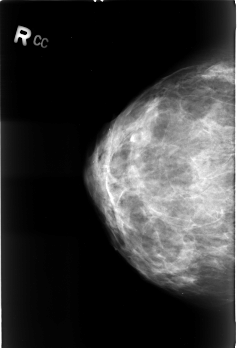

B_3033_1.RIGHT_CC

RIGHT_CC LINES 4512 PIXELS_PER_LINE 3072 BITS_PER_PIXEL 12 RESOLUTION 50 NON_OVERLAY